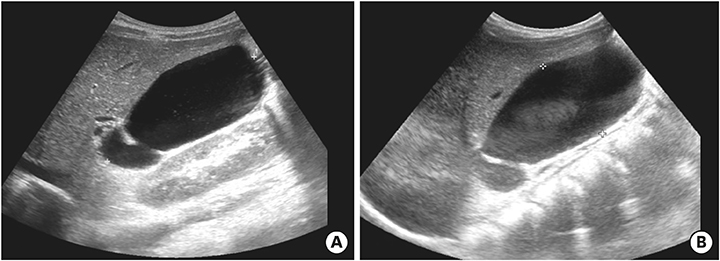

After discharge and 23 days of fever onset, a follow-up abdominal sonography revealed a slower regression of the GB hydrops (Fig. 5A). Echocardiography performed at 81 days after onset of fever revealed complete improvement of both the coronary artery lesion and GB hydrops (Fig. 5B).

Fig. 5

Abdominal ultrasonography (A) performed at 23 days after fever onset revealed a slow regression of the gallbladder hydrops (6.7×3.2 cm in size). Echocardiography (B) performed at 81 days after fever onset revealed a complete improvement in gallbladder hydrops and a normal gallbladder.